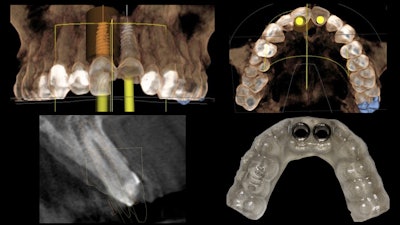

We merged the patient's two datasets (teeth and soft tissue and also osseous information) using implant treatment planning software. From this we developed a prosthetically driven virtual surgical plan. At that point, we also designed a surgical guide that was 3D-printed in advance of the implant placement surgery (figure 2).

We determined that tooth #8 was restorable on caries excavation, so a full-contour composite buildup was done (the guide sleeve for #8 was removed from the surgical implant guide). Next, tooth #9 was extracted atraumatically.

Then we used a prefabricated surgical guide to direct the osteotomy drill sequence, immediately placing the NobelActive implant fixture (Nobel Biocare) in a fully guided fashion (figure 3).